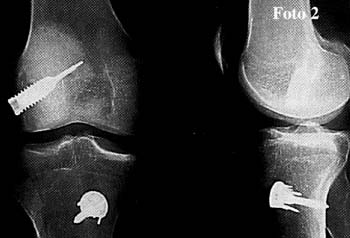

Fotos 1 y 2

El promedio de edad fue de 30 arios (rango entre 18 y 45 anos); distribucion por sexo, 218 sexo masculino y 54 femenino.